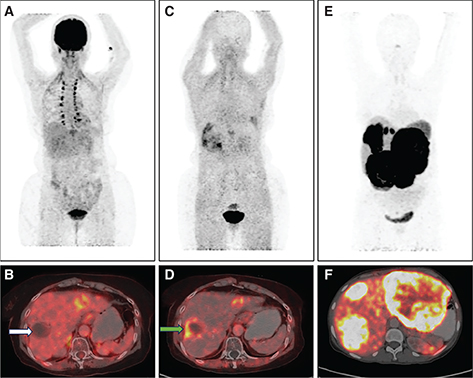

Various PET quantitative parameters such as SUV, metabolic tumor volume (MTV) and tumor lesion glycolysis (TLG) accurately detect the baseline tumor bulk and total body disease burden and have a significant role in disease prognosis and management (48). The primary tumor SUVmax is an independent prognostic factor for survival outcomes in CCA and for predicting metastases on follow-up (48). Calculating volumetric parameters is tedious and time consuming, however technological advances in the form of automated volumetric analysis and threshold-based segmentation have made it more convenient. Newer acquisition techniques like dynamic 18F-FDG PET imaging have shown to be superior to conventional imaging in detecting and excluding CCA in advanced PSC with lesion/liver ratio being significantly higher in parametric images than static PET images (49). Not only can it help to differentiate normal from malignant tissue, kinetic modeling and analysis also helps to differentiate hepatocellular cancer from CCA (50). Figure 3 shows 18F-FDG PET-CT findings in common BTCs.

Fig 1

Figure 3. 18F-FDG PET/CT in biliary tract cancers: A) Maximum Intensity Projection (MIP) image showing focal intense tracer uptake in the region of the gallbladder fossa (black arrow). Corresponding CT (B) and fused PET/CT (C) images show intensely tracer avid (SUVmax 28.7) heterogeneously enhancing mass lesion arising from the fundus and body of the gallbladder with local invasion (Gallbladder carcinoma) (white arrows). D) MIP image showing tracer uptake in the region of the liver (black arrow) with corresponding CT (E) and fused PET/CT (F) images showing 18F-FDG avid (SUVmax 11.2) hypodense lesion in the right lobe of liver (white arrows) causing intrahepatic biliary radical dilatation suggestive of intrahepatic cholangiocarcinoma along with percutaneous transhepatic biliary duct stent in situ in the left ductal system (dotted arrows). G) MIP image with no abnormal focus of uptake seen anywhere in the region of the liver. Corresponding CT (H) and fused PET/CT (I) images show faintly tracer avid biliary ductal thickening (SUVmax 5.1) in the hilar region with tracer uptake similar to background liver uptake suggestive of hilar cholangiocarcinoma.